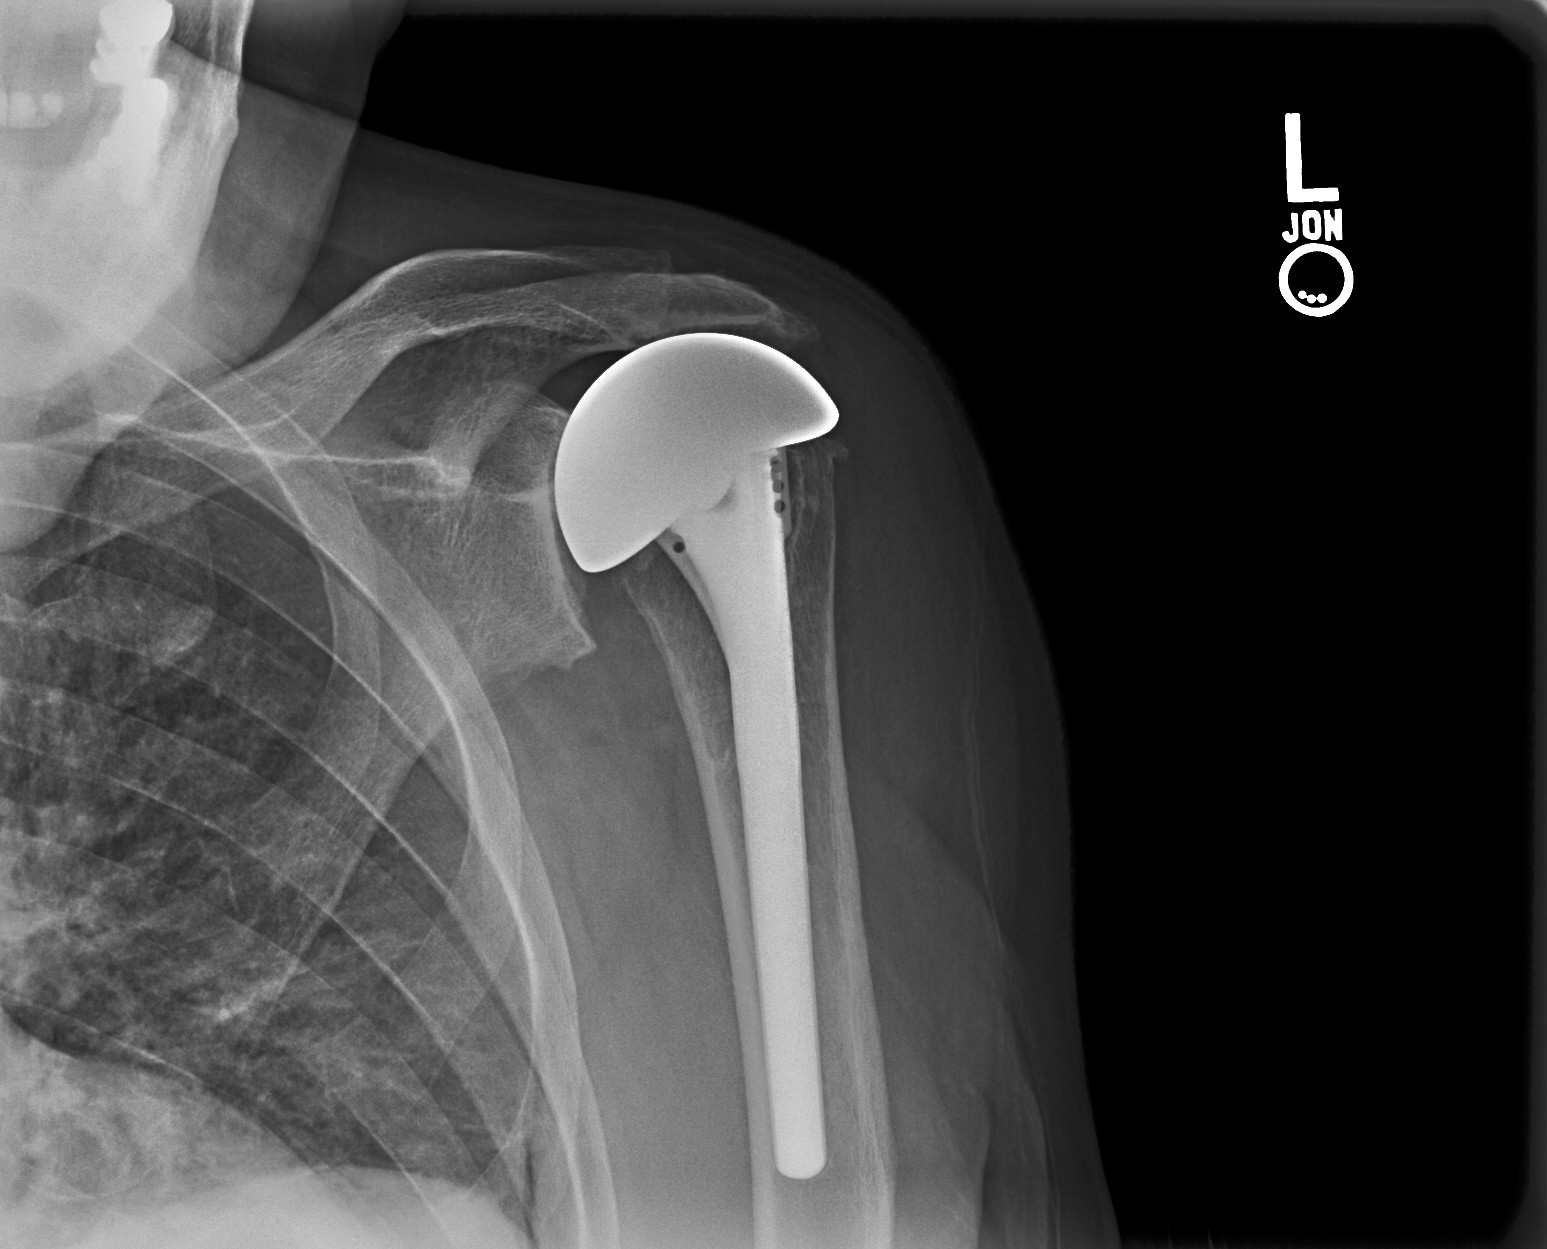

Partial or Total Shoulder Replacement Dr Skedros Orthopaedics Rotator Cuff Tear Shoulder X Ray Rcta has three major characteristics: Rotator cuff tears are a common cause of shoulder pain. Radiopaedia.org explains the causes, types, and radiographic features of rotator cuff tears, common shoulder pain causes. Clinical and radiographic findings can suggest the presence of a rotator cuff tear. The rotator cuff (rc) is a group of four muscles and tendons surrounding the shoulder joint. Rotator Cuff Tear Shoulder X Ray.